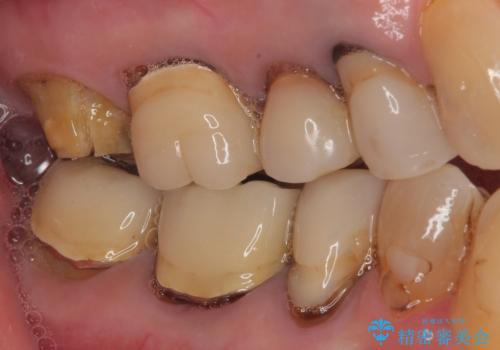

抜歯後2ヶ月でのインプラント埋入を行いましたが、骨の再生は不十分でした。

骨量は不十分でしたが、デンサーバーを用いることで無事に埋入することができ、その後は速やかに補綴治療を行うことができました。